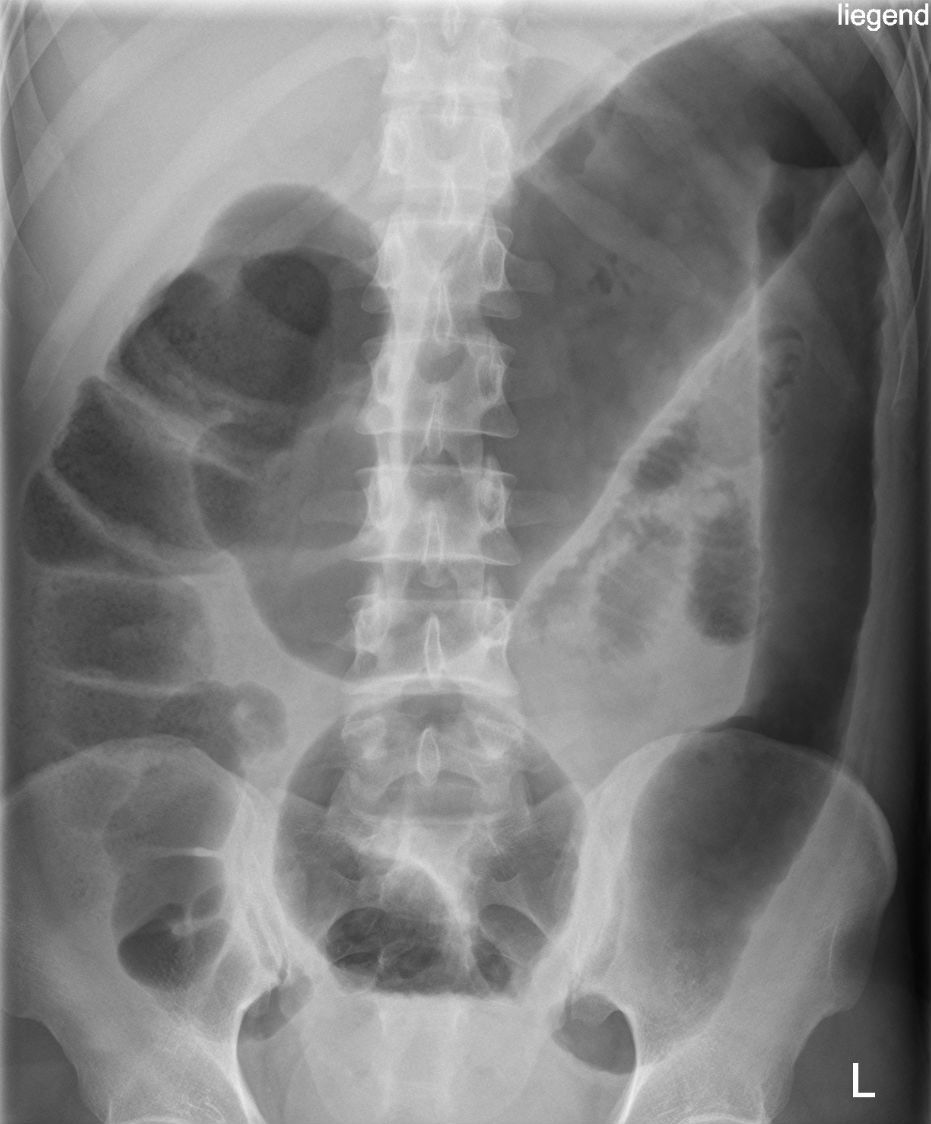

What should you look for on abdominal xray to confirm toxic megacolon?